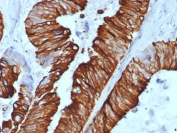

IHC staining of FFPE human colon carcinoma tissue with Cytokeratin 20 antibody (clone KRT20/7805R). HIER: boil tissue sections in pH 9 10mM Tris with 1mM EDTA for 20 min and allow to cool before testing.

Applications Immunohistochemistry (FFPE) : 1-2ug/ml for 30 minutes at RT

This mAb recognizes an intermediate filament protein of 46kDa, identified as cytokeratin 20 (KRT20). KRT20 is abundantly expressed in goblet cells and enterocytes of the gastrointestinal tract. It is a useful marker of pancreatic and colorectal cancer. KRT20 is expressed under normal, hyperplastic and neoplastic conditions. It has been detected in adenocarcinomas of the colon, stomach and biliary tract. Breast carcinomas are generally non-reactive.